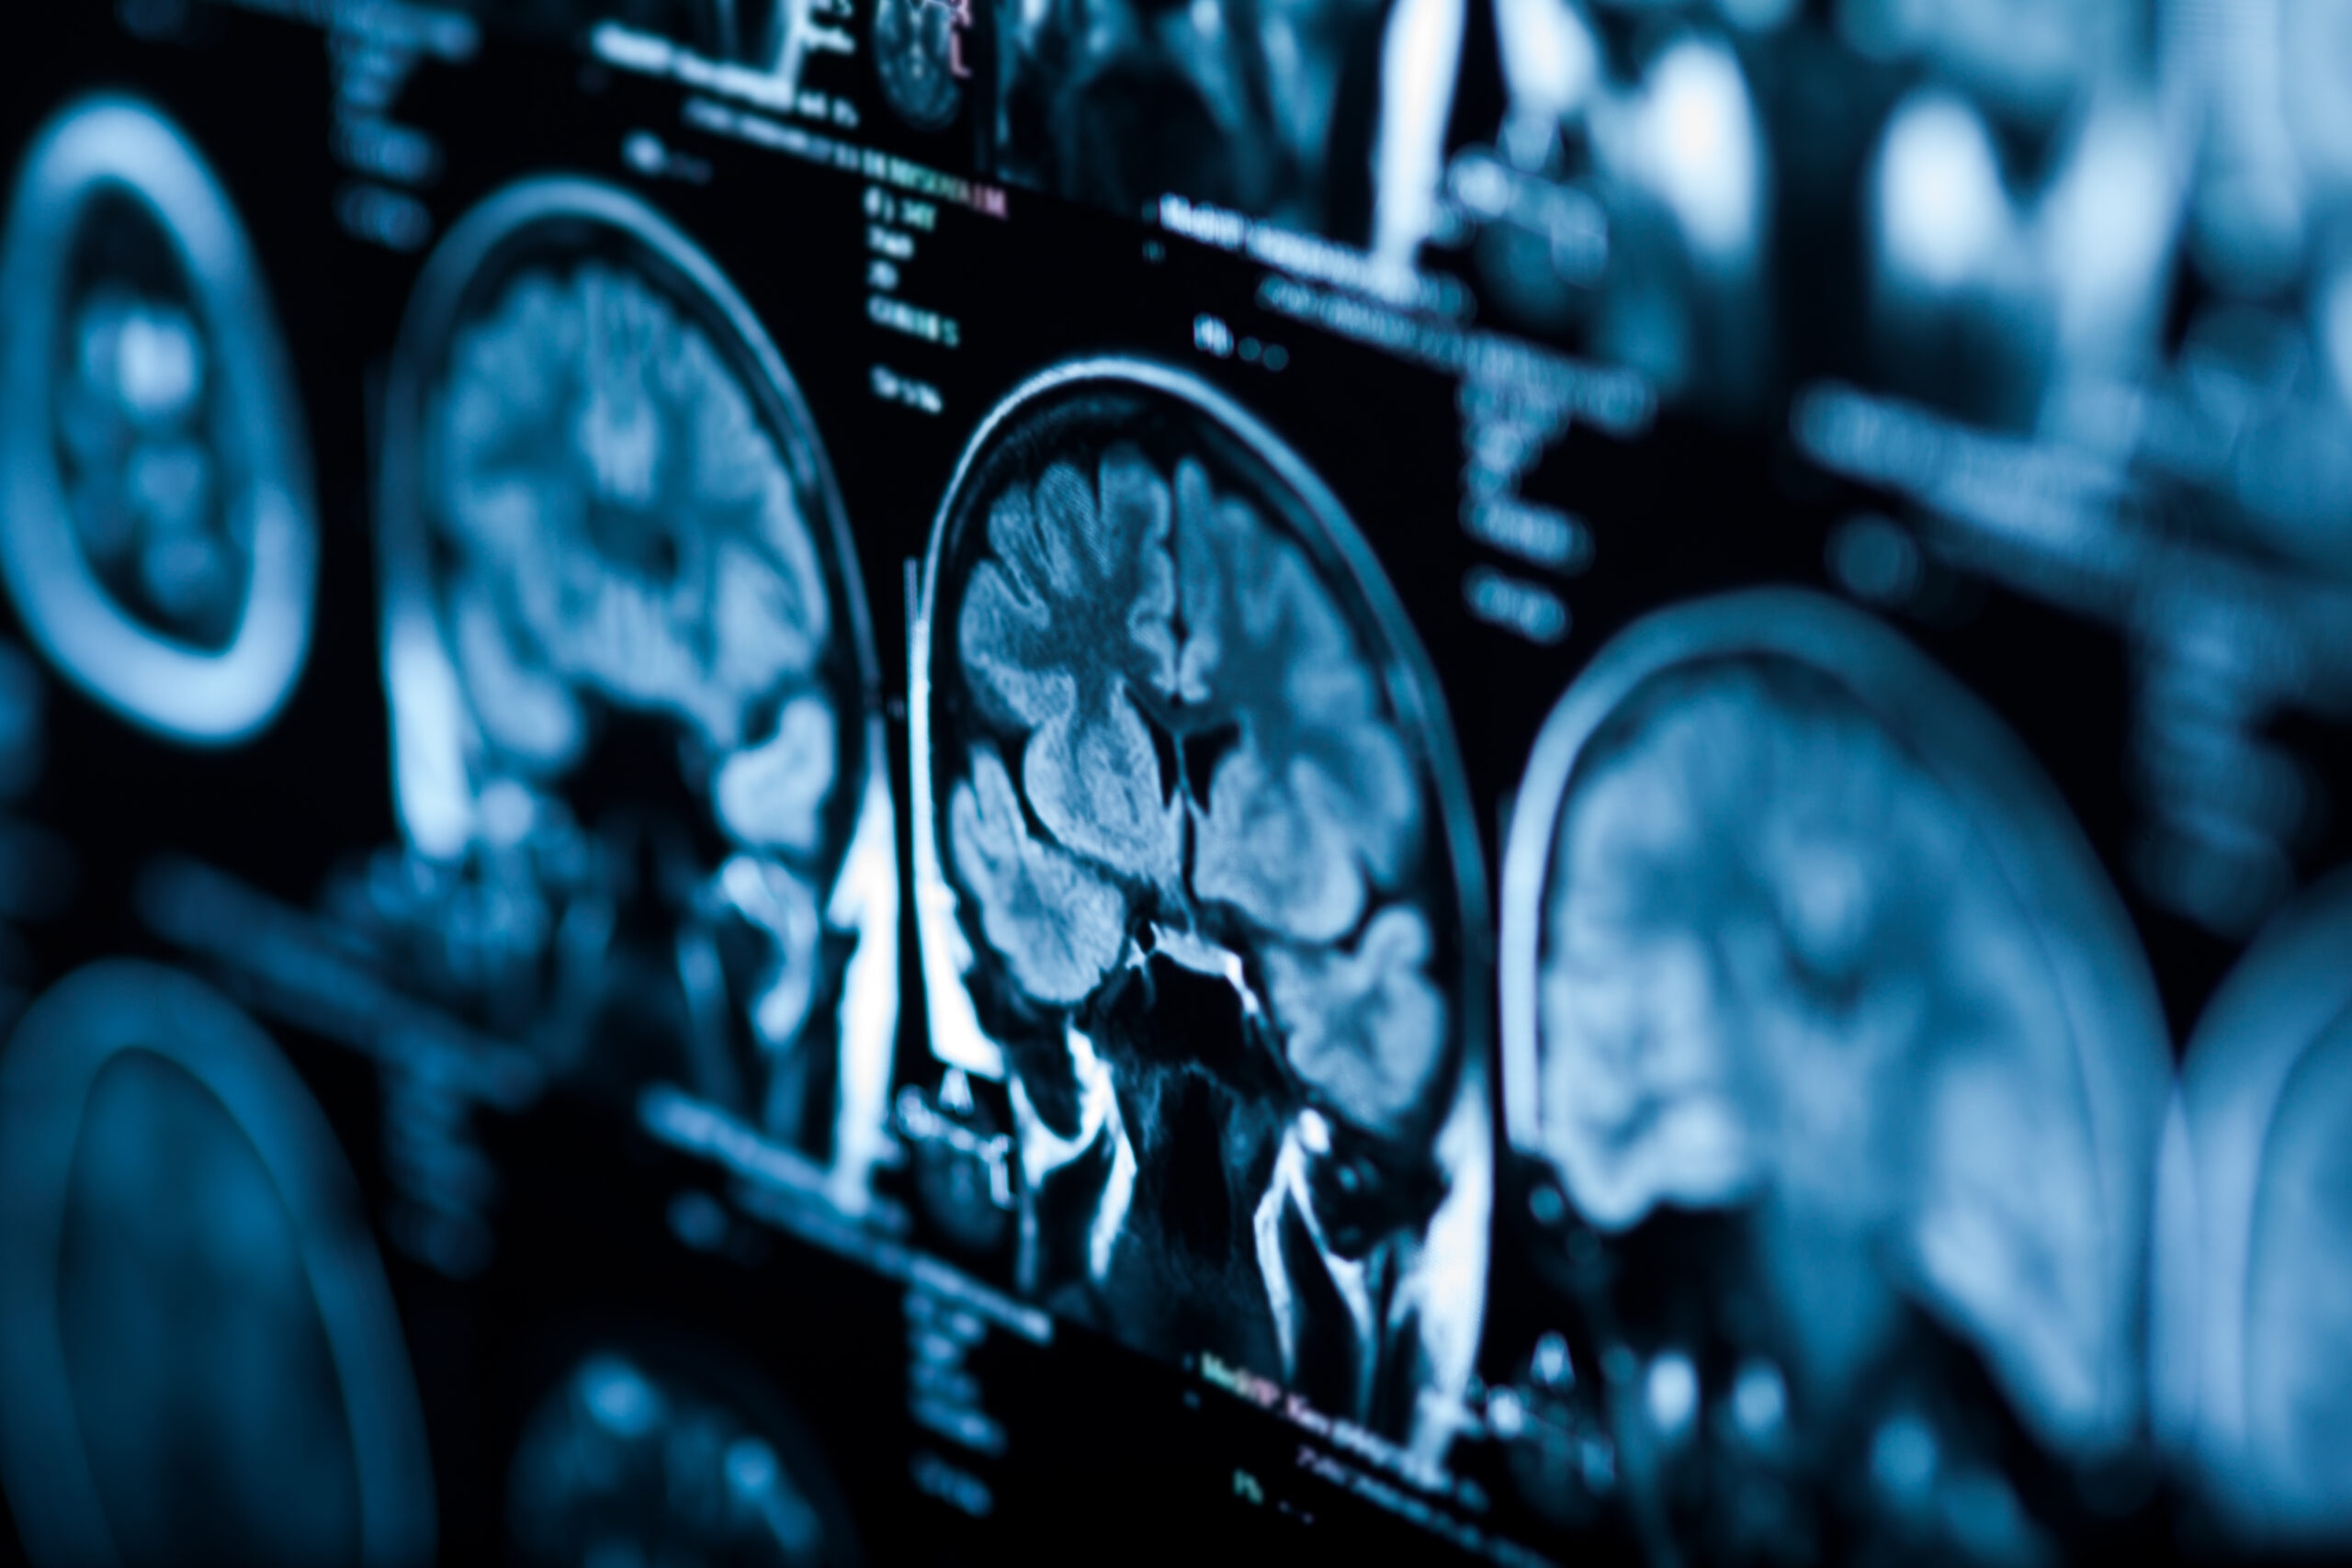

Neurocognitive & brain health

TPE may help reduce circulating inflammatory and protein factors associated with cognitive decline, brain fog, and certain neurodegenerative processes.